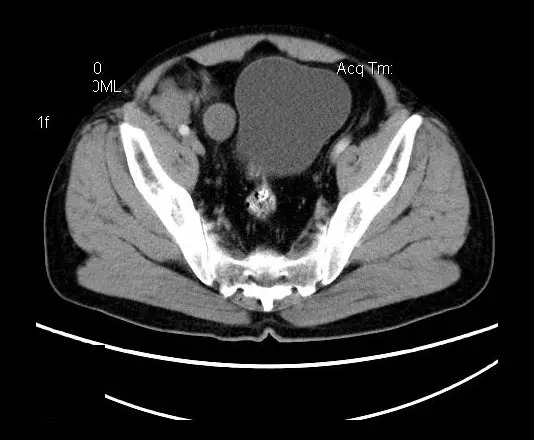

【影像表现】

盆腔右前侧及邻近腹股沟区可见多发大小不等的聚集生长的结节影,病灶呈软组织密度,边缘尚规整,分界尚清,增强扫描可见不均匀强化。膀胱局部受压,盆腔未见明显肿大淋巴结影。

神经鞘瘤显微镜下主要由AntoniA区和Antoni B区按不同比例构成,也可主要只含某种成分。免疫组化S-100蛋白多为阳性反应。肿瘤易发生退变(囊变,出血及钙化)

盆腔神经鞘瘤的影像学表现主要取决于肿瘤本身细胞不同组成分布及排列(Antoni A区与B区不同比例)及肿瘤是否发生退变所致。Antoni A 区由密集的梭行细胞构成,细胞核排列为栅栏状或漩涡状。Antoni B区瘤细胞稀疏,网状排列,基质含水量高,常发生囊变或出血。

平扫影像表现:Antoni A区较多病灶,在CT上呈等或略高密度影,T1WI等信号、T2WI略高信号,AntoniB区较多病灶,CT多为水样低密度、T1WI低信号、T2WI明显高信号。

增强影像表现:神经鞘膜肿瘤增强后,由于Antoni A区与B区以不同比例混合而强化不一,呈不均匀斑片状,条状强化。Antoni A 区富血供,中等或明显强化,Antoni B区乏血供,强化多不明显。